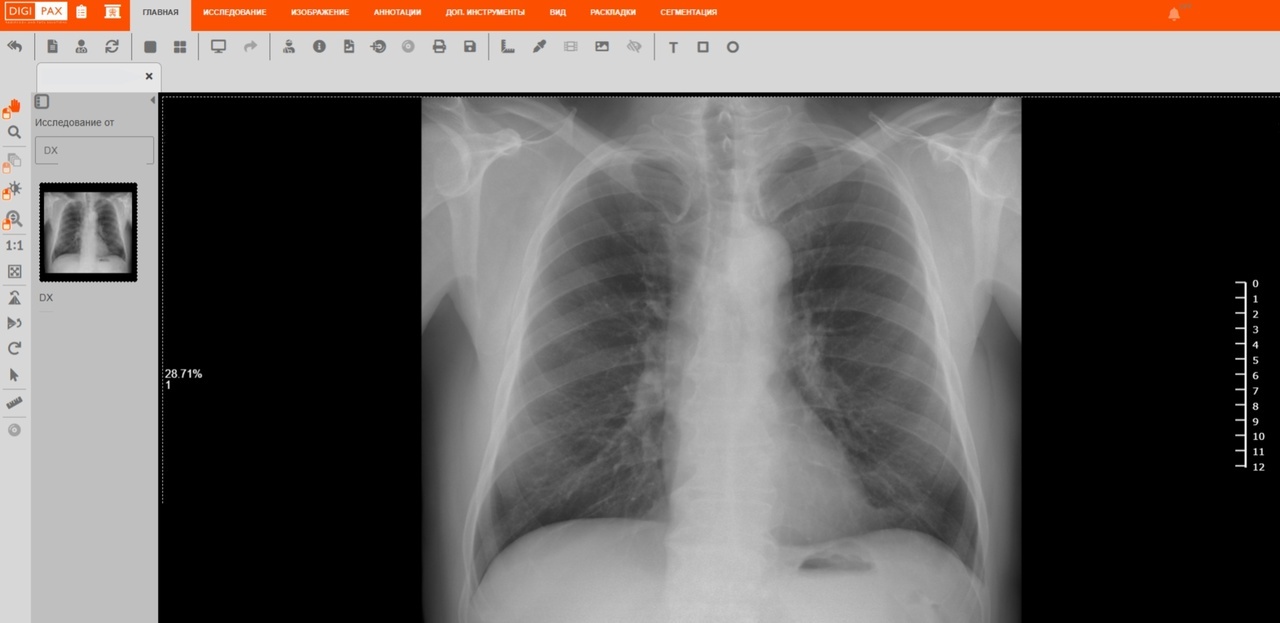

В ноябре медицинские специалисты Вологодской области получили доступ к инновационной системе, которая автоматически обрабатывает результаты компьютерной томографии, рентгенографии и маммографии с использованием искусственного интеллекта московской платформы «МосМедИИ». Эта технология позволяет быстро выявлять на снимках изменения, указывающие на возможные патологии, и составлять подробные заключения, что улучшает диагностику и качество медицинского обслуживания. Интеграцией региональной информационной системы и этого цифрового помощника занималась компания «Ростелеком» совместно со своим дочерним предприятием «РТК Радиология».

В начале компания установила более 100 диагностических устройств в 30 государственных медицинских учреждениях, среди которых больницы, поликлиники и диспансеры в Вологде и Череповце. Затем был налажен электронный обмен рентгеновскими снимками между местной системой здравоохранения и московской платформой. Всего за первый месяц работы с новой платформой на основе искусственного интеллекта было обработано свыше трех тысяч медицинских изображений: рентгеновских снимков, маммограмм и результатов компьютерной томографии.

Применение платформы «МосМедИИ», работающей на базе искусственного интеллекта, обеспечивает высокую скорость и точность обработки медицинских изображений (до 95%). Эта система может анализировать большие объемы данных, автоматически маркировать обнаруженные патологии и составлять подробные заключения.

В планах в будущем году — рассмотреть вопрос о подключении к сервисам «МосМедИИ» по расшифровке снимков рентгенографии и компьютерной томографии органов грудной клетки, — Михаил Кузнецов, заместитель министра здравоохранения региона.